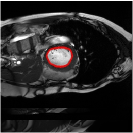

4.4 Comparison with cardic MR images for left ventricle segmentation

In this section, we continue to conduct experiments on cardiac MR images. However, we focus on the right ventricle, which is equally important as the left ventricle in cardiac MR diagnoses. In the near short-axis view, the left ventricle has a crescent shape, while the right ventricle is closer to circular. This does not imply that the right ventricle is easier to segment; in the MR images we use, the right ventricle often shows low-signal-intensity shadows, which may be caused by the imaging characteristics of certain tissues or fluids, leading to interference in segmentation. Moreover, there is a layer of myocardial tissue surrounding the right ventricle that overlaps with the boundary of the right ventricle, posing challenges for accurate identification.

Fig. 8 presents the segmentation results of the right ventricle from the DRLSE-ADMM [WALI2023109105], ABC model [WENG2021115633], RESLS [8765635], the RefLSM, and the ground truth. The results from the DRLSE-ADMM model in the 1st row reveal severe local minima due to low-signal-intensity shadows in the right ventricle. Additionally, both the ABC and RESLS models fail to correctly identify the right ventricle boundary because of the interference from surrounding myocardial tissue, as seen in the 1st and 3rd columns of Fig.8. In comparison, the proposed model gets more satisfactory segmentation results that are closer to the ground truth. Similarly, we evaluate the segmentation performance of all models by calculating the Dice and Precision values and drawing Fig. 9. This overlay plot presents the best, median and worst segmentation results, along with the overall range of outcomes that it is clear that the proposed model segments the right ventricle with greater accuracy than the other models and performs well in different images.